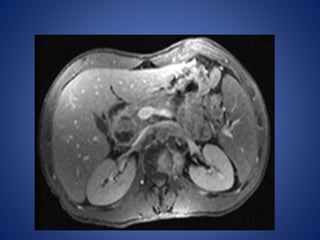

Thickened ileocaecal bowel

Computer tomography scan

48